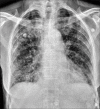

Background: Chest radiography (CXR) is a widely available baseline radiological modality in evaluating symptomatic patients with suspected or confirmed Covid-19 disease. Serial changes can help in monitoring the patients in conjunction with the clinical status of these patients in a hospital setting.

Purpose: The purpose of this study was to analyse the patterns of radiological findings on chest radiograph (CXR) for suspected and confirmed COVID-19 patients on initial presentation to the emergency medical services (EMS) on admission and to assess the progression and resolution.

Results: 756 RT-PCR confirmed COVID-19 patients were included in our study who had initial CXR. 510 (67.46%) of our patients with positive initial RT-PCR showed abnormal baseline CXR. The abnormal findings were described as haziness akin to ground glass opacities (GGO) on CT, peripheral opacities, patchy parenchymal opacities and consolidation. Peripheral opacities and lower zone distribution were the commonest pattern of CXR abnormalities with bilateral involvement. The severity of findings on serial CXR and radiographic regression was studied along with follow-up to assess response to treatment. Forty-six patients showed features of acute lung injury (ALI). Complications and new CXR findings were reported for patients who were given ventilator support.

Conclusion: CXR is a valuable baseline radiological investigation on hospital admission in symptomatic patients with suspected or confirmed Covid-19 presenting to the EMS as it helps to monitor the progress and regression of the disease in conjunction with clinical findings.